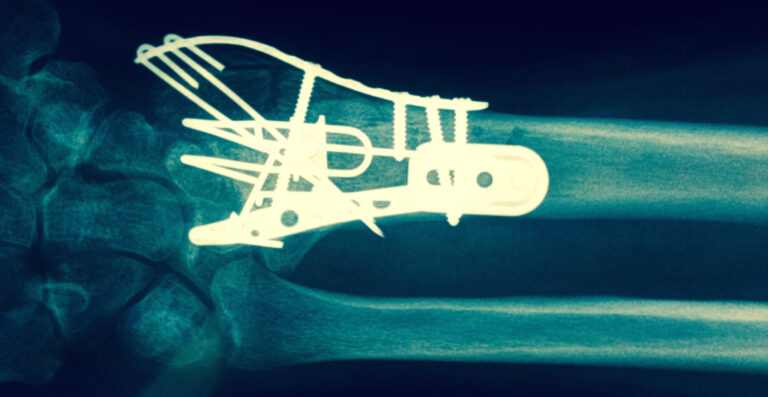

Surgical Approach

When there is displacement or the Broken Wrist Colles’ Fracture cannot be stabilised following manipulation then surgery may be required. The Hand Therapists, Physiotherapists and Occupational Therapists at Action Rehab are experienced in treating post surgical Broken Wrists. It is important that you seek Hand Therapy following your wrist surgery in order to limit your post operative complications, increase your function and return to sport or work sooner.

See below the two treatment approaches for a patient who has broken wrist.